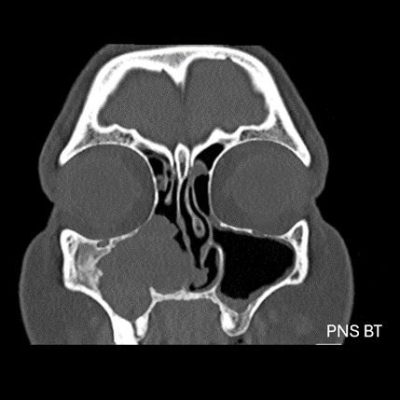

- A) Koronal T2 ağırlıklı görüntülerde sol maksiller sinüs lümenini dolduran, belirgin ‘convoluted’ (karmaşık-kıvrımlı) serebriform patern sergileyen lezyon (oklar), kontrastlı seride heterojen ve yoğun kontrastlanma göstermektedir (oklar). Perfüzyon incelemesinde pedinkülünde perfüzyon artışı gösterdiği, diğer kontrastlanan segmentlerin nispeten hipoperfüze olduğu görülmektedir (ok).

- B) BT incelemesinde maksiller sinüsün duvarları özellikle lateralde daha belirgin olmak üzere reaksiyonel kalınlaştığı izleniyor (oklar). DWI ve ADC haritasında lezyonda belirgin bir kısıtlılık görülmemektedir (oklar).

- Tümörün köken aldığı bölgede fokal hiperostoz görülebilir. Sinüs duvarlarında erozyon olabilir ancak bu genellikle tümör basısına veya eşlik eden inflamasyona sekonderdir, direkt invazyon kesin değildir. Kalsifikasyon beklenen bir bulgu değildir (olursa atipi veya malign transformasyon akla getirilmeli)